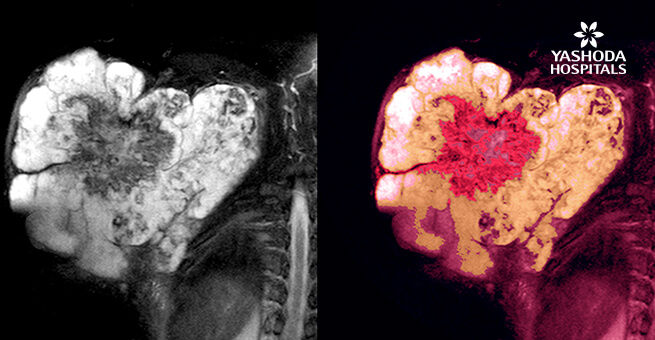

- The doctor advises imaging tests depending on the situation. Tests that are advised are X Rays which are done to diagnose problems in the bone, MRI is done to diagnose connective tissue problems and other tests like CT scan, bone scans and PET (positron emission tomography) can be advised further.

- BIOPSY- This is a procedure done to remove a piece or remove a sample from the suspicious tissue for testing in the lab. These tests help in determining the nature of the cells ,whether they are cancerous or non- cancerous and help in choosing the best treatment. The collection of a biopsy sample depends entirely on the situation of the disease. Most of the biopsies that are done are closed biopsies or as outpatient procedures by the radiologist under guidance.

- In a soft tissue sarcoma several types of growths that are abnormal in nature can be seen and these are called malignant tumors or cancer. In such malignant growths, the tumor breaks off and spreads into the surrounding tissues in the body ,lodging themselves in the lungs, liver , brain or other organs.